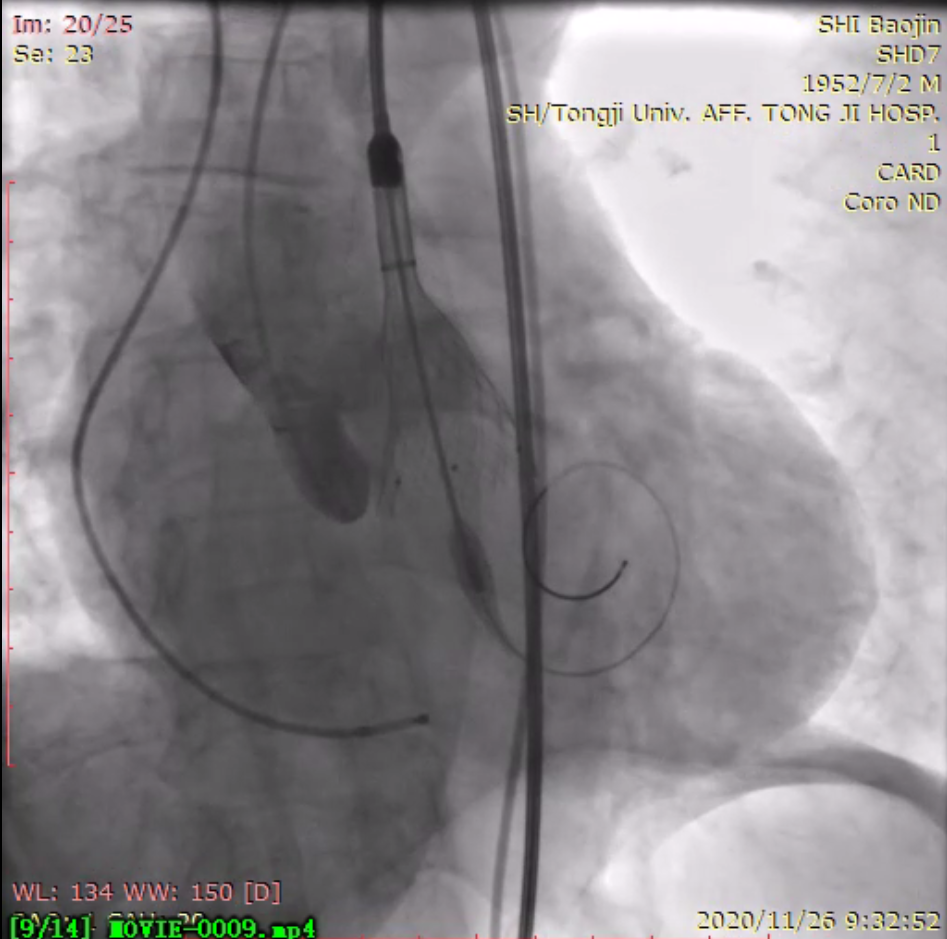

瓣膜释放中

同济大学附属同济医院党委书记许树长、院长程黎明到心脏导管室进行了关心慰问。术中患者主动脉跨瓣压差 67 mmHg,根据术前 CT 评估瓣环直径和术中球囊预扩张情况,选择合适的人工瓣膜,一次精准定位释放,复查跨瓣压差消失,实时食道超声心动图见轻微瓣周漏,效果良好,整个手术一气呵成。